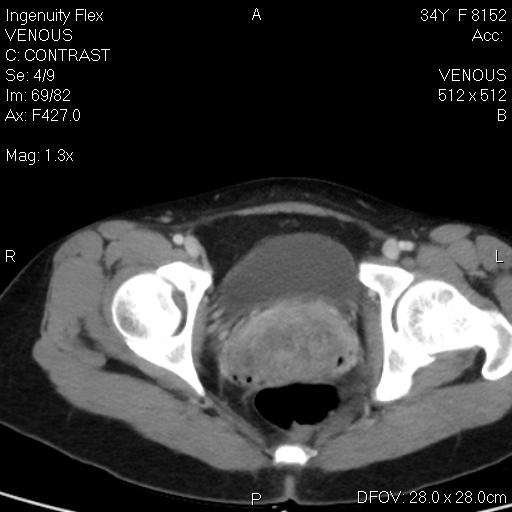

CT-ung thư cổ tử cung

CT-ung thư cổ tử cung 2

CT-ung thư nội mạc tử cung